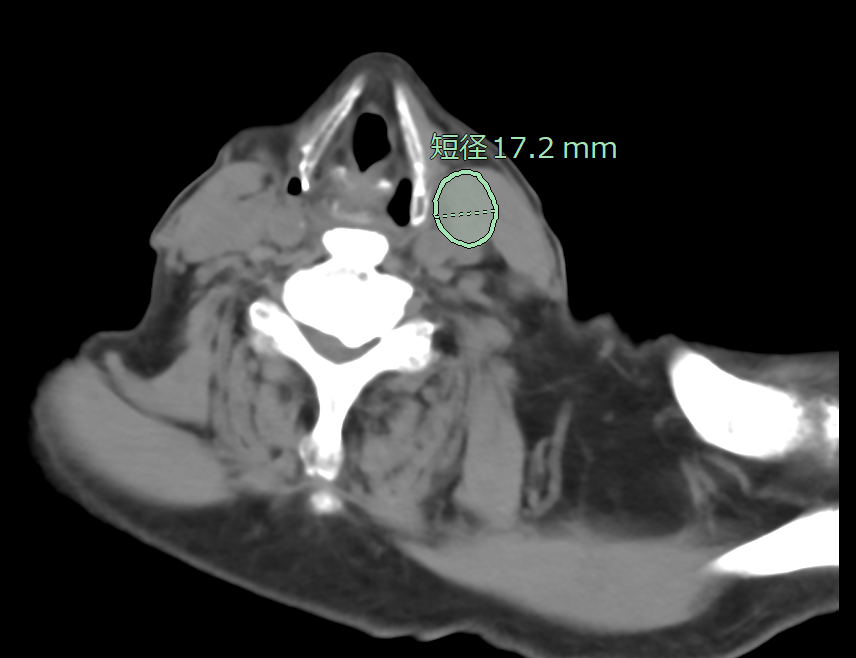

リンパ節は全身に存在しており、想定外の箇所が腫大することもあるため、読影に大きな負担がかかっています。従来、CT画像(造影・非造影)において、縦隔・腋窩リンパ節の抽出が可能でしたが、今回、頸部・腹部(大動脈周囲、骨盤部)でもリンパ節の抽出ができるように対象範囲を拡充しました。縦隔・腋窩だけではなく、頸部・腹部も含めた箇所における腫大傾向のリンパ節を拾い上げ、自動で短径計測を行います。癌の転移検索の支援に繋がることが期待されます。

頸部CT画像でのリンパ節抽出